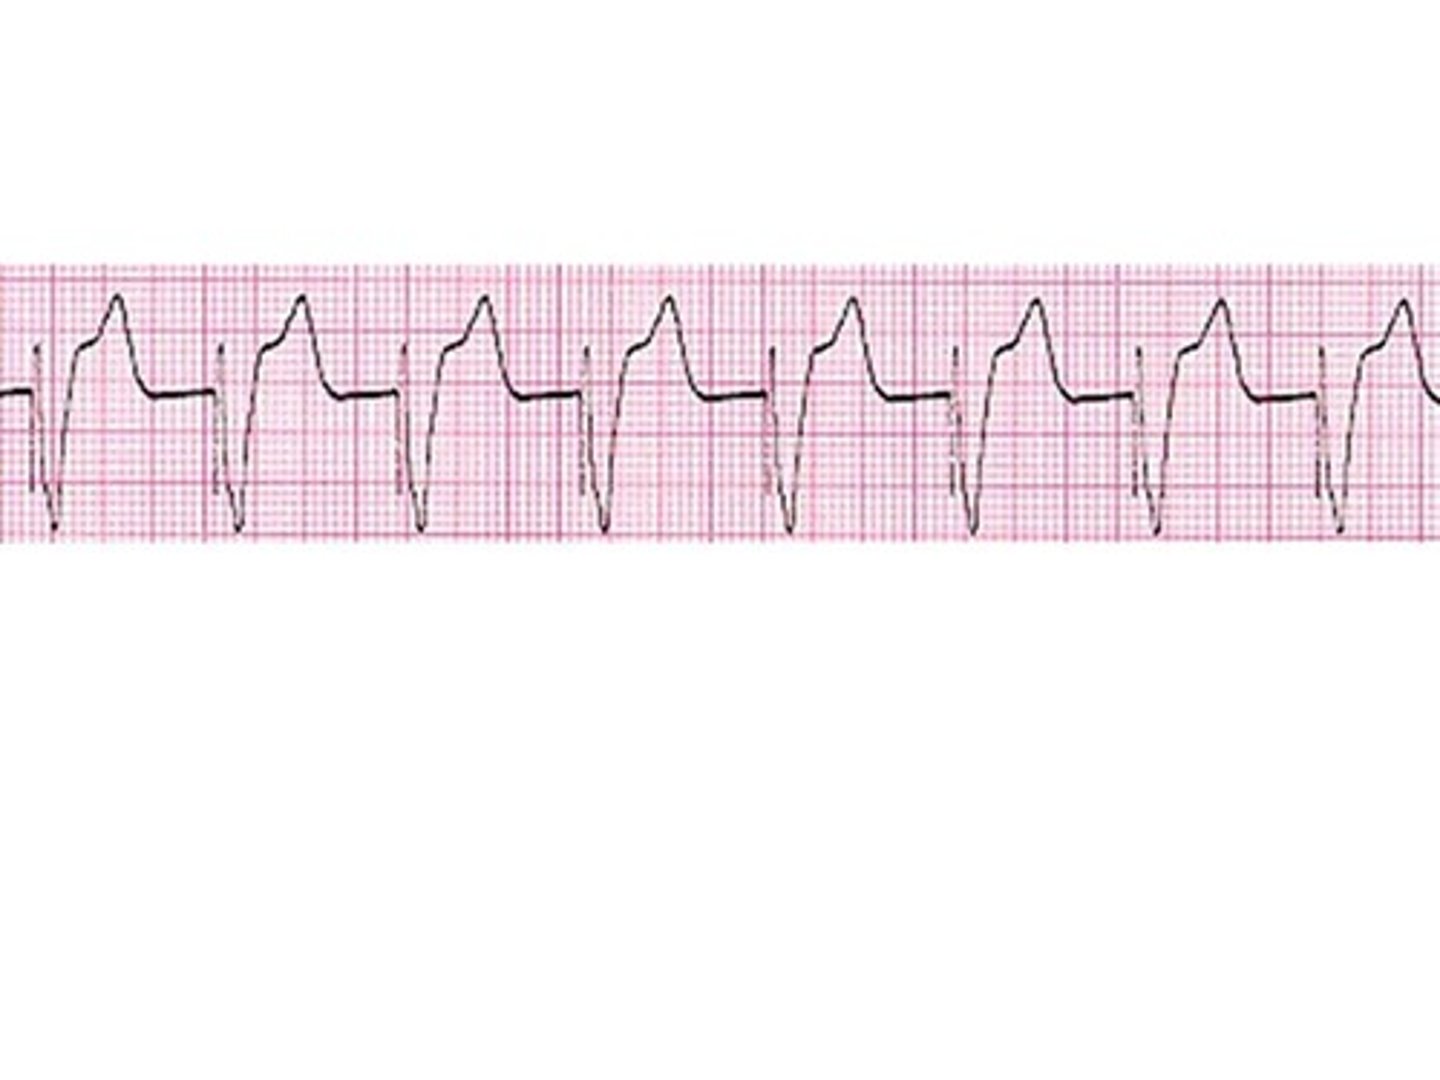

What is v tach?

BAD, ventricles are pumping too fast

What is the treatment for v tach?

Stable: O2, amiodarone, correct electrolyte imbalances

Unstable: cardioversion, O2

no pulse: defibrillate